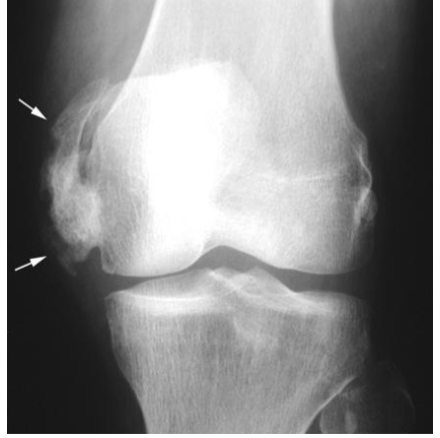

Osteoarthritis= Most Common

Osteoarthritis is also called as degenerative joint disease

affects cartilage (the tissue that cushions and protects the ends of bones in a joint) - with osteoarthritis, the cartilage wears away over time

bone-on-bone contact

bones may also bulge, or stick out at the end of a joint= bone spur

joint pain and can limit ROM (the ability to freely move and bend a joint)